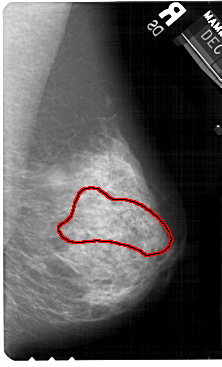

A_1511_1.LEFT_CC

LEFT_CC LINES 5491 PIXELS_PER_LINE 3271 BITS_PER_PIXEL 12 RESOLUTION 43.5 NON_OVERLAY

FILE: A_1511_1.RIGHT_CC.OVERLAY

TOTAL_ABNORMALITIES 1

ABNORMALITY 1

LESION_TYPE CALCIFICATION TYPE AMORPHOUS DISTRIBUTION SEGMENTAL

ASSESSMENT 4

SUBTLETY 3

PATHOLOGY BENIGN

TOTAL_OUTLINES 1

BOUNDARY